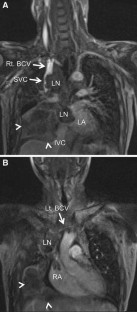

Fig. 3